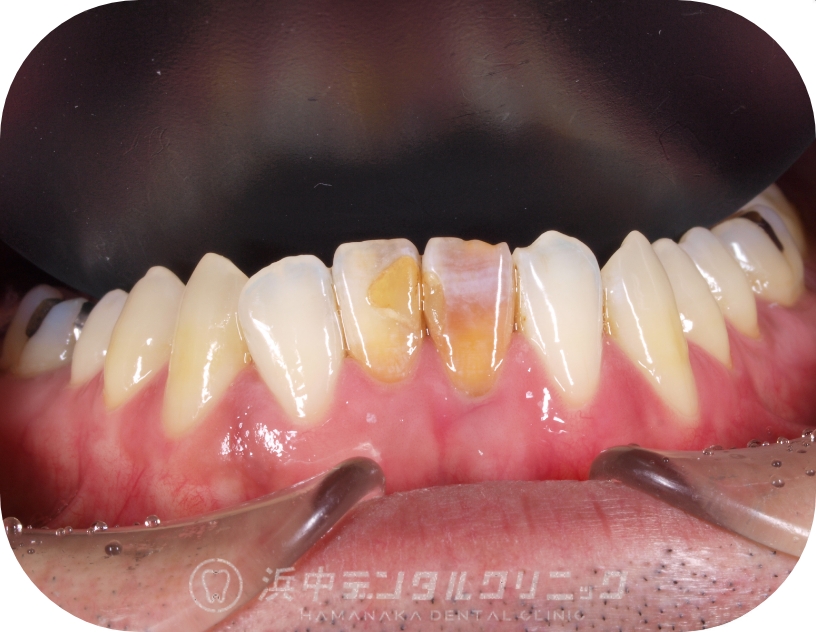

過去神経を抜いた前歯が変色してきたのが気になり、前歯2本をジルコニアセラミックで審美治療した症例(40代男性)

BEFORE

患者様の主訴

昔に神経を抜いた下の前歯の色が黒くなってきたのが変色が気になる。

診断結果

神経を抜いた歯の変色と、変色した古い詰め物による審美障害が生じてました。

治療内容

最初に該当歯2本をマイクロスコープでの精密根管治療を行い、その後ウオーキングブリーチで内部より漂白を行ったが、完全には白くならなかったので、患者様がジルコニアセラミックでの審美治療をご希望されたので、グラスファイバーポストを築造して、シリコンによる精密印象を行い、ジルコニアセラミックを接着しました。

治療後経過

アフターの写真は術後4年経過の写真だがセラミックの欠けなど無く、非常に歯肉とも調和しており経過良好です。

| 治療期間 | 約2ヶ月 |

|---|---|

| 治療費用 | 保険の精密根管治療費+ジルコニアセラミック(176,000円×2本) |

| 治療のリスク・副作用 | 歯根の破折やセラミックのチッピング(欠け)が生じる場合があります。 |